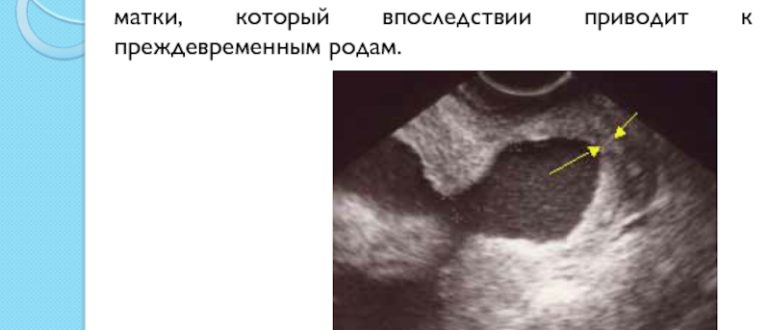

Воронкообразное расширение